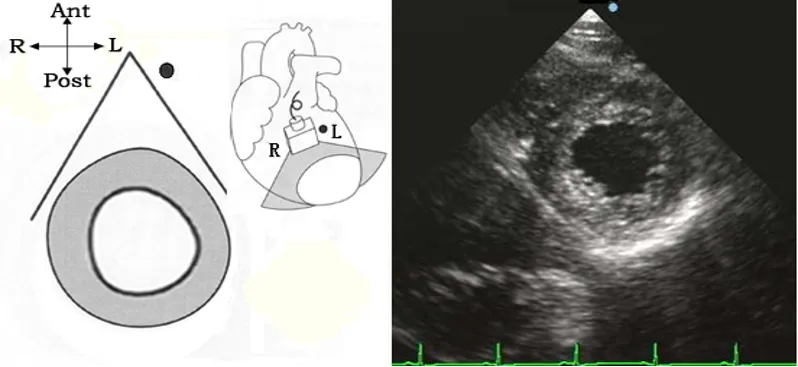

胸骨旁二尖瓣口水平短轴切面

● 探头位置:探头置于胸骨左缘3、4肋间,声速恰好通过二尖瓣口。

● 观察内容

1:瓣膜活动:二尖瓣形态结构,活动和测量二尖瓣瓣口面积。

2:室壁厚度:基底部整个左室壁。

3:室壁活动:基底部整个左室壁。